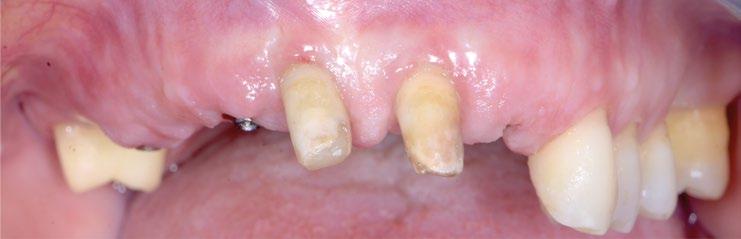

Se presenta el caso de un paciente varón de 48 años de edad, ASA II, fumador que acude a consulta por la pérdida de su incisivo central superior derecho (Figura 1).

A la exploración clínica se observa enfermedad periodontal estadio III grado B con múltiples ausencias dentarias posteriores de larga evolución que han ocasionado la migración de los dientes adyacentes y antagonistas generando múltiples prematuridades e interferencias. Como consecuencia de todo ello, el paciente ha perdido el diente 1.1 con pérdida de volumen de tejido y el 2.1 presenta movilidad grado III con pronóstico imposible (Figura 2).

En la exploración radiográfica en 3D (CBCT) se aprecia ausencia de cortical vestibular en 2.1 y un defecto óseo horizontal en 1.1 (Figura 3).